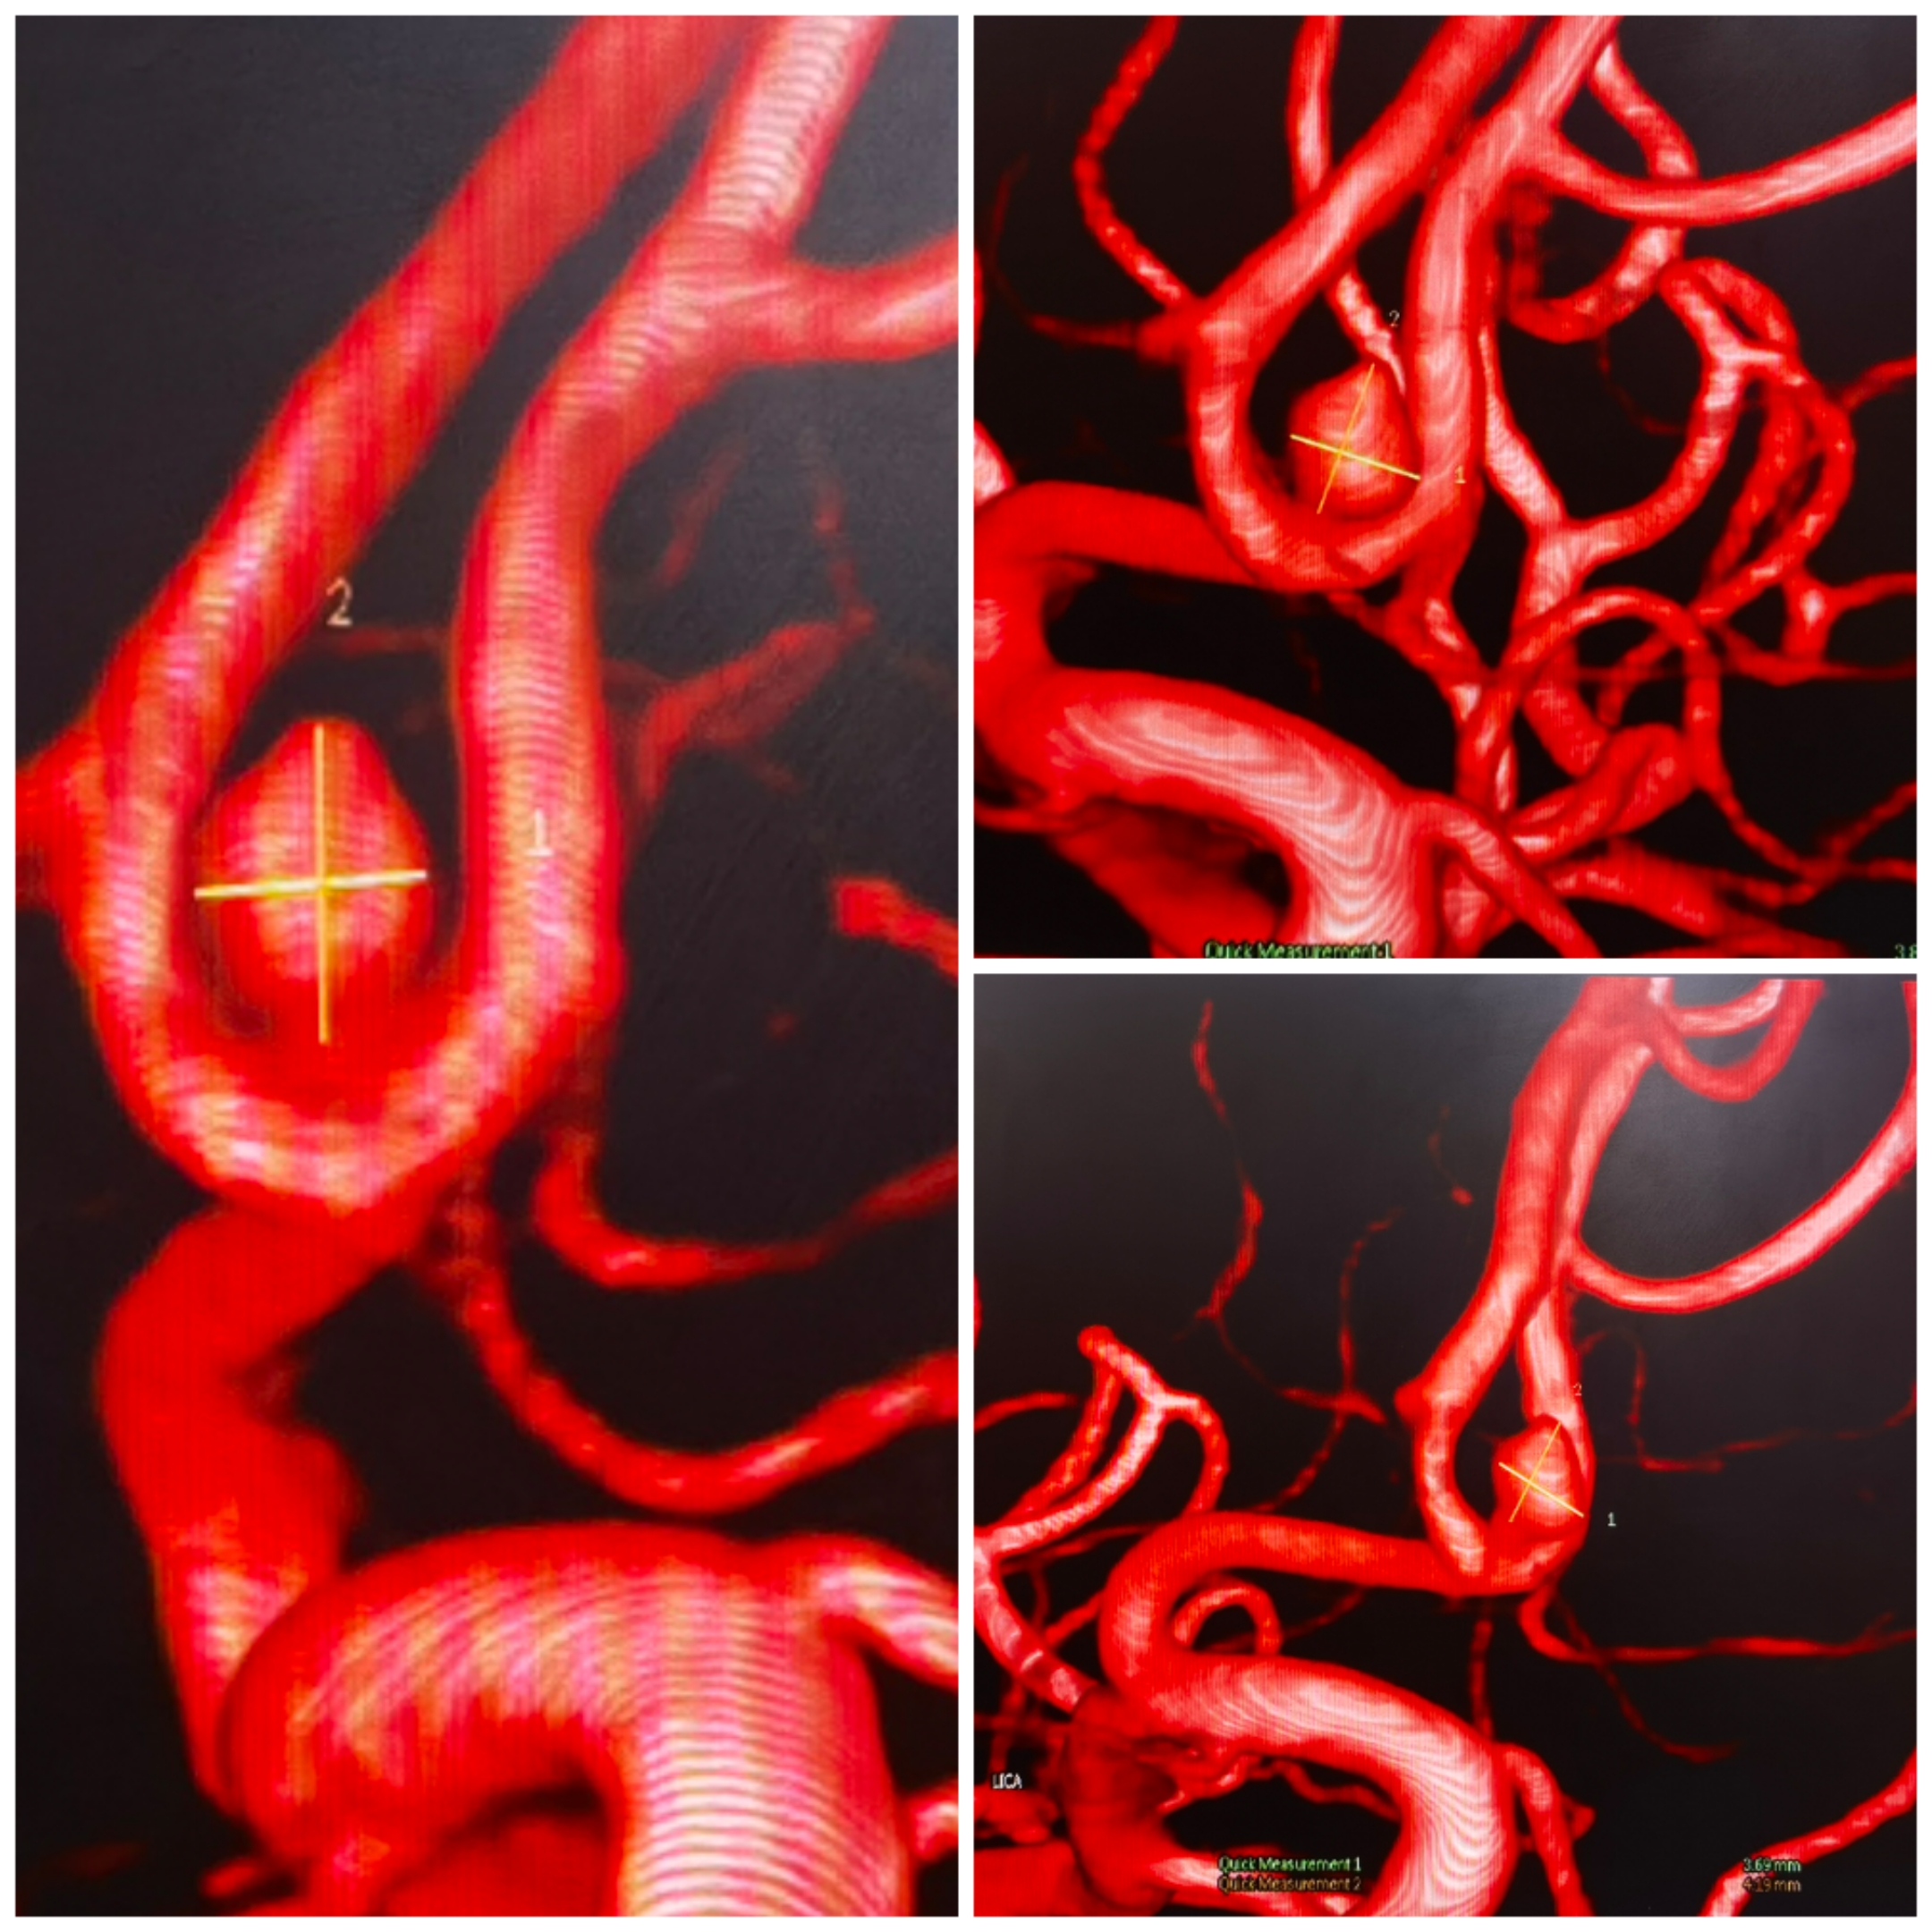

CTA提示前交通动脉瘤,双侧A1发达,似乎是宽颈的

3D重建情况